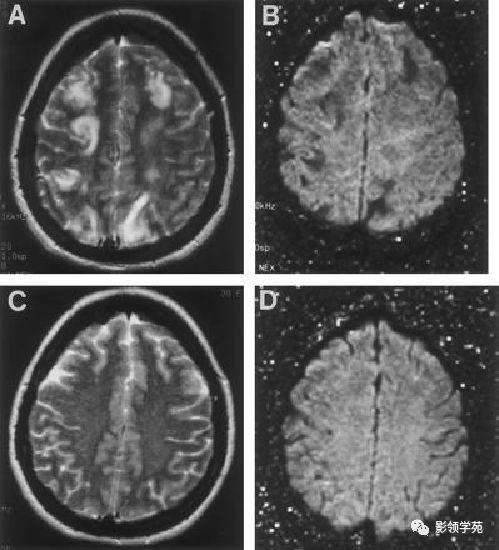

脑白质病变影像诊断

脑室周围白质软化早产儿出生早期mri表现及其演变

脑白质成像影像特征与常规mri比较